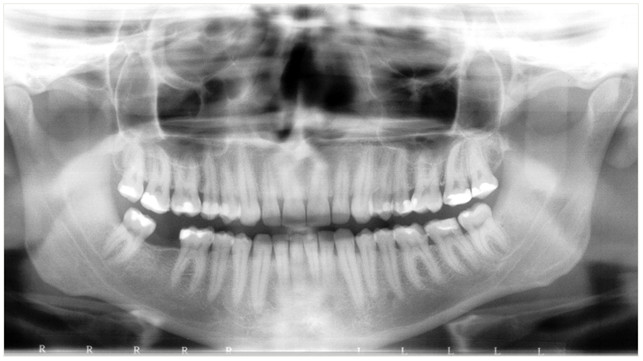

Na przedstawionym poniżej zdjęciu pantomograficznym można zauważyć nietypowy wygląd prawego siekacza centralnego w żuchwie. Obraz ten sugerować może:

Pytanie 43